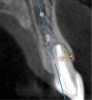

The patient, a healthy 45-year-old nonsmoking woman (American Society of Anesthesiologists [ASA] II), presented with a failed maxillary central incisor due to severe internal-external root resorption (Figure 1). She had a high esthetic risk profile based on 12 presenting esthetic risk factors (key No. 1), including a high lip line, high esthetic expectations, and adjacent teeth that had been restored (Figure 2).Site-specific CBCT (Carestream CS 9300, Carestream Dental, carestream.com) noted a thick intact buccal plate and a class 1 sagittal root position (Figure 3 and Figure 4). Preplanning with a bone-level 4.1-mm diameter x 14-mm long implant (Straumann Bone Level Roxolid® SLActive, Straumann, straumann.com) assured a 3-mm buccal gap upon placement and a screw-retained position (key No. 2). Prior to placement, intact buccal and palatal walls were confirmed. Figure 5 shows palatal wall placement of the implant after minimally traumatic flapless tooth extraction. An anatomically correct surgical guide template was used to assure a screw-retained position and correct vertical depth of approximately 4 mm from the mid-buccal apical extent of the guide template, which correlated to 1 mm apical of the intact buccal plate (key Nos. 3 through 5). The two-unit (8-9x cantilever) fixed provisional was recemented post-surgery. The 3-mm buccal gap was grafted tightly with a low-substitution DBBM (Bio-Oss®, Geistlich Pharma, geistlich-na.com) (key No. 6), and a pouch was created with a Buser membrane instrument (Hu-Friedy, hu-friedy.com) from line angle to line angle as a mini full-thickness flap to the mucogingival border to accept a connective tissue graft (Figure 6). The connective tissue graft, 1-mm thick x 12-mm long x 7-mm wide (Figure 7), was harvested from the palate (key No. 7).

Fig 5. Palatal wall placement of implant. Anatomically correct surgical guide template assured a screw-retained position and correct vertical depth.

Figure 5